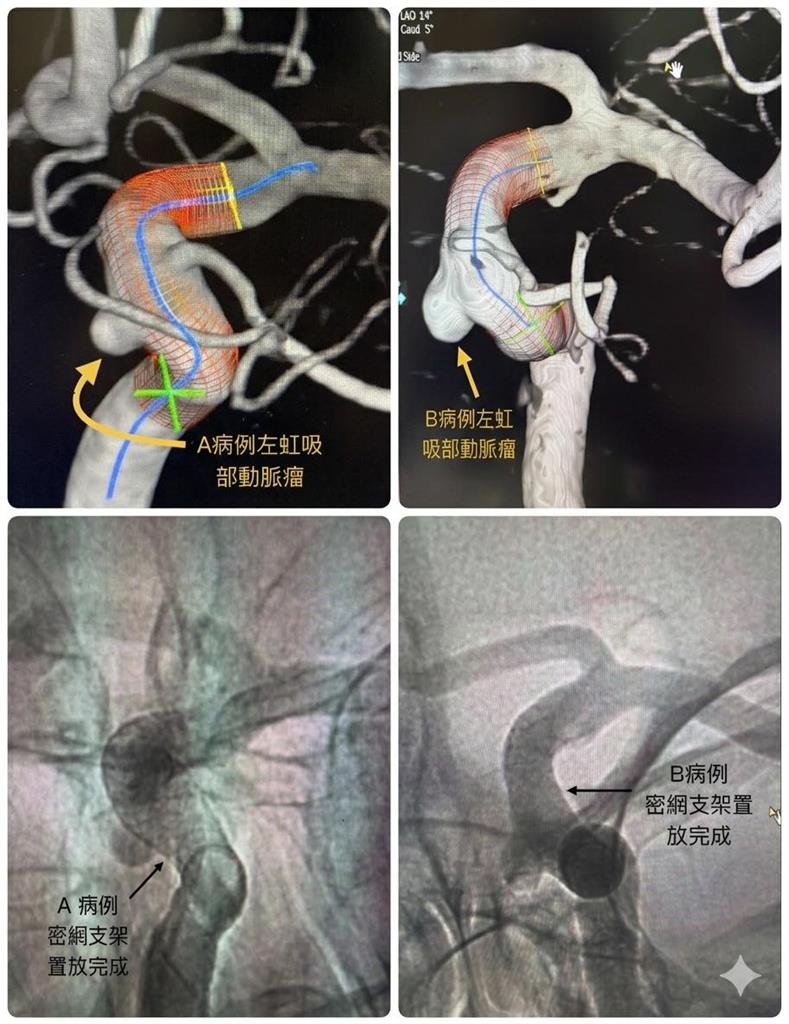

陳啟仁在臉書發文指出,這兩名患者皆接受未施打顯影劑的MRA腦血管檢查,結果都在左邊相同位置「虹吸部」發現動脈瘤。後續經血管攝影確認診斷後,兩人皆選擇接受自費「密網支架置放」微創手術,且原本還希望安排同一天進行手術,兩人的家人還可以分工來陪,最終因排程因素作罷。更令人驚訝的是,醫師在術後與患者閒聊時才得知,兩人不僅是好友,過去還曾在同一家公司工作,而當年的老闆在40多歲時,曾因劇烈頭痛與嘔吐送醫,最終不治,院方推測極可能為動脈瘤破裂所致。

陳啟仁在臉書發文,2名同公司好友竟在腦部同一位置長動脈瘤,連前老闆也疑似因此猝逝。(圖/翻攝自陳啟仁臉書)

「真的好巧」 兩位近50歲的朋友(A及B)不約而同因頭漲漲的來做不打藥的MRA...